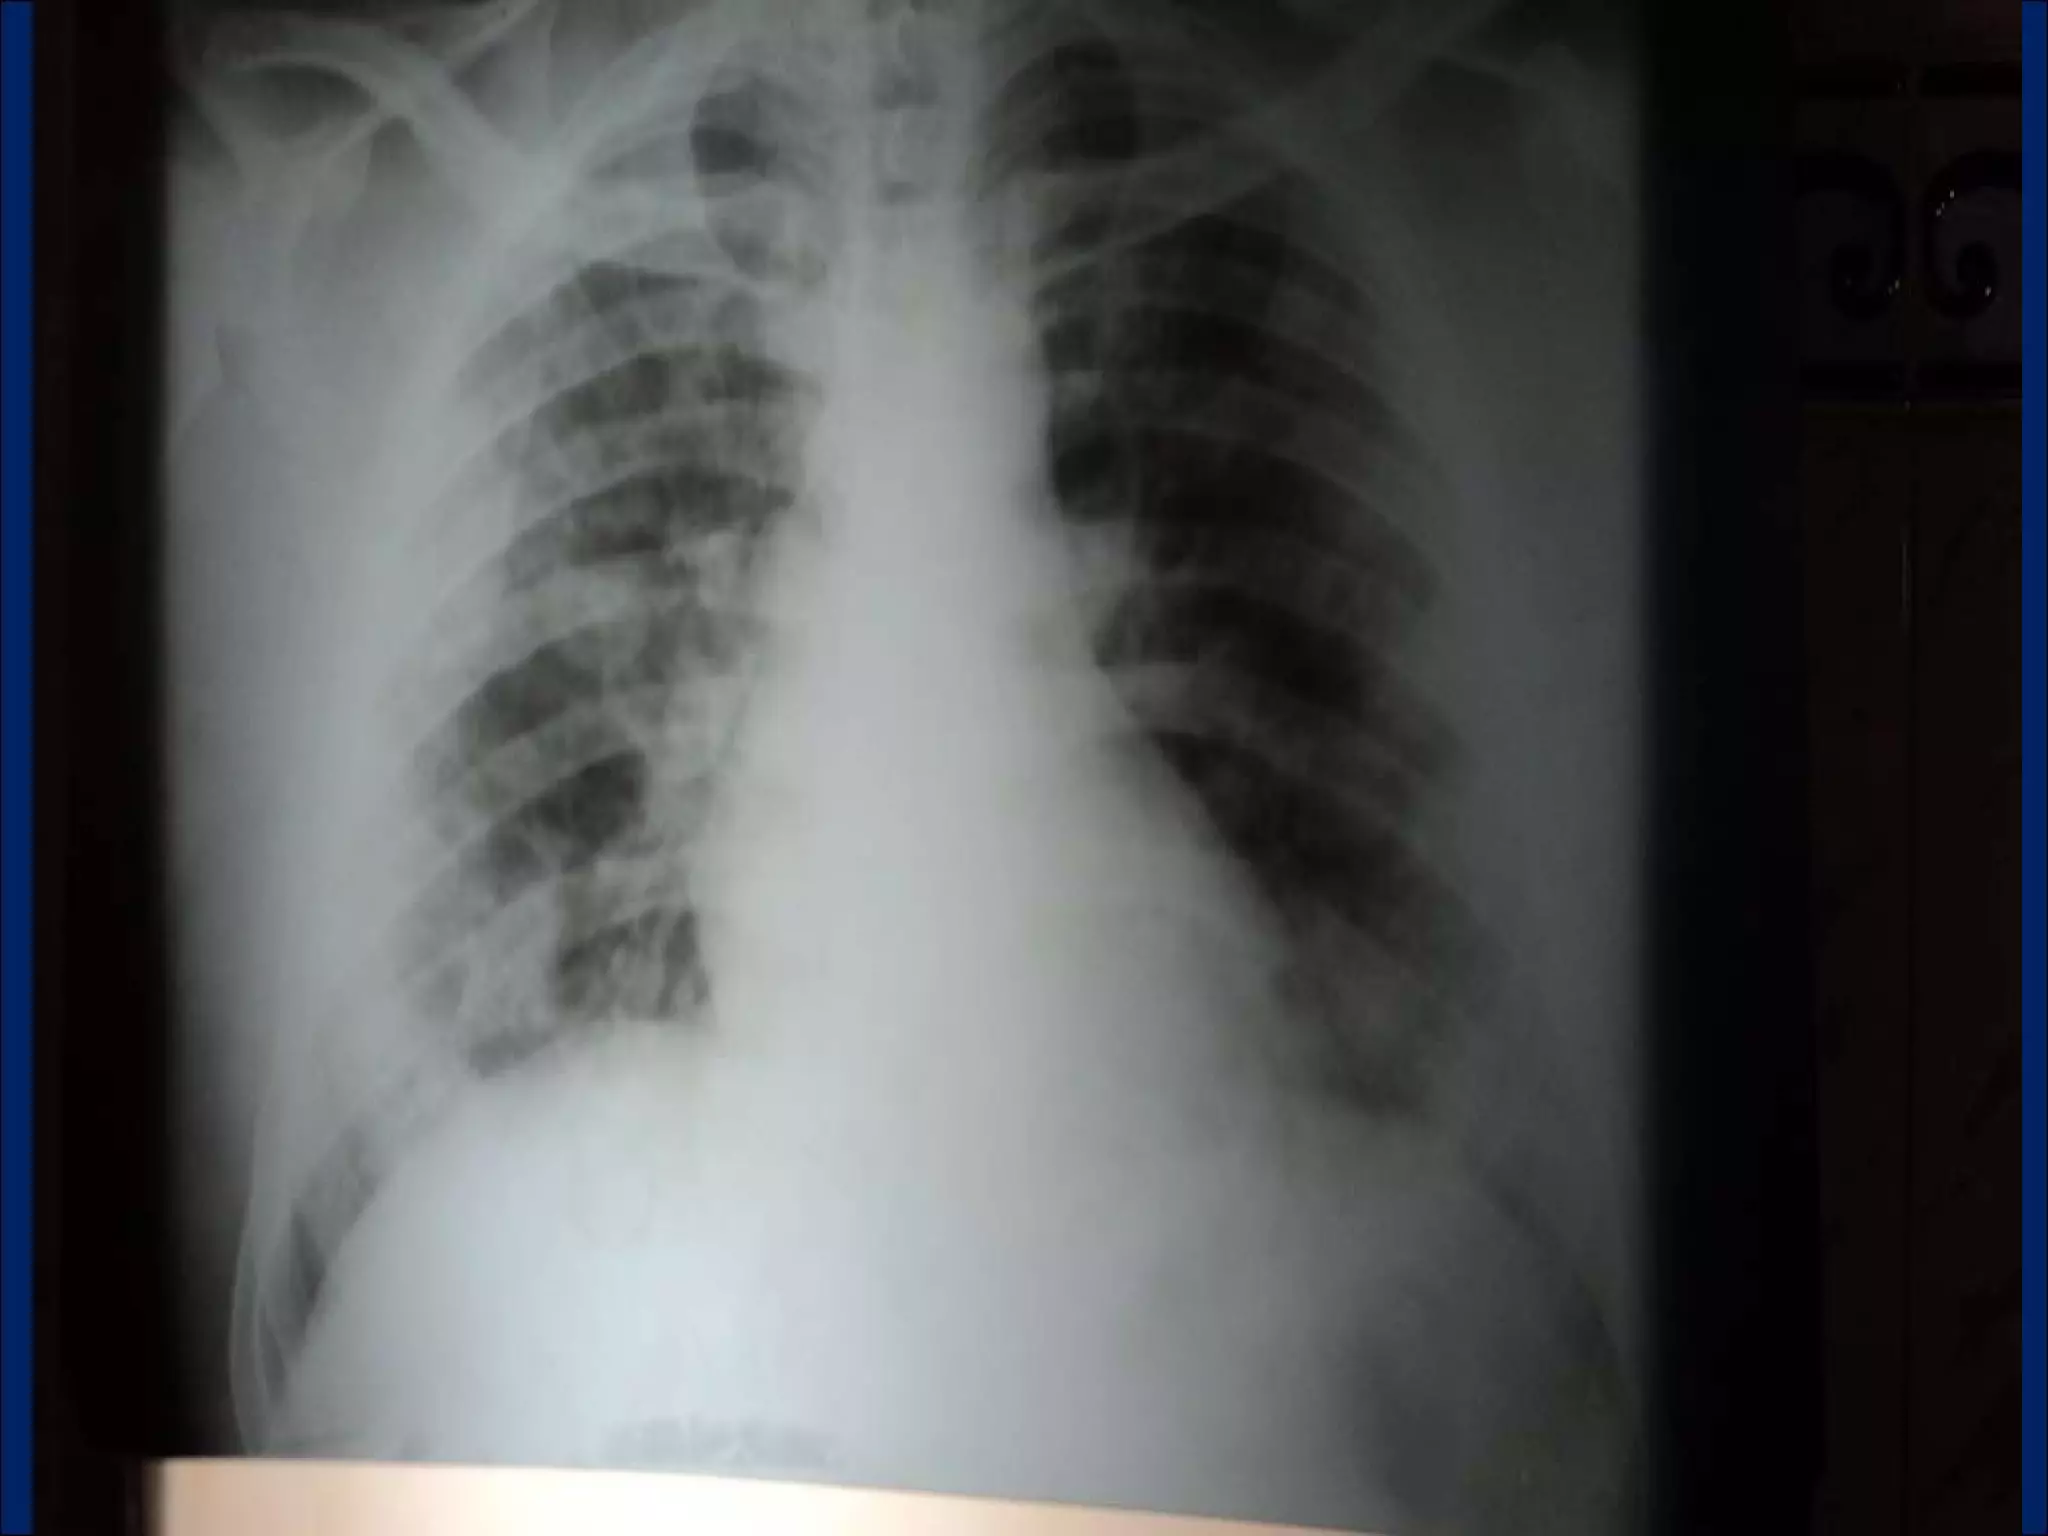

Imaging: Multiple Pulmonary Cavitary Lesions

LOOKING  AT  CAVITIES What is the anatomic distribution?  Is It single or multiple?  If multiple , are they focally located or diffusely seen in multiple lobes of both lungs? Is are the characteristics of the cavity? Is the cavity wall thick or thin? Is the interior lining nodular, shaggy, or smooth? Are there any other associated radiographic abnormalities?